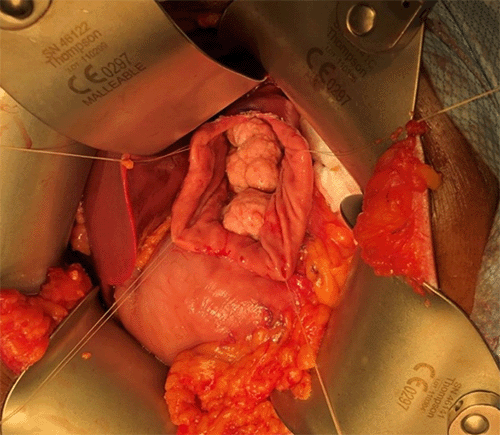

Given the known association between gastric xanthoma and gastric cancer as well as the symptomatic nature of the condition, the decision was made to pursue extirpation of the mass via partial gastrectomy. After performing upper endoscopy in the operating room, multifocal masses were visualized. The abdomen was entered via an anterior open approach with an upper midline incision and the mass was palpated. There was no extraluminal extension. A large anterior gastrotomy was made, and the multifocal xanthoma (three in total) were removed separately by externalizing them anteriorly through the gastrotomy and transecting the base with a gastrointestinal loaded stapler (Figures 2A and 2B). The anterior gastrotomy was then closed with a handsewn technique. Gross pathology measured the three specimens as 9 cm x 3.7 cm; 14 cm x 3 cm; and 0.5 cm x 0.3 cm. Final surgical pathology confirmed that all three specimens were consistent with xanthoma. There was no dysplasia or malignancy identified in the specimens, and the margins were free of xanthoma. The patient recovered well postoperatively. To our knowledge, this case represents the largest gastric xanthoma reported in the medical literature.

Figure 2. Multifocal Gastric Xanthoma Visualized Through Anterior Gastrotomy. Published with Permission

Multiple, yellowish lesions consistent with gastric xanthoma are evident on the gastric mucosa